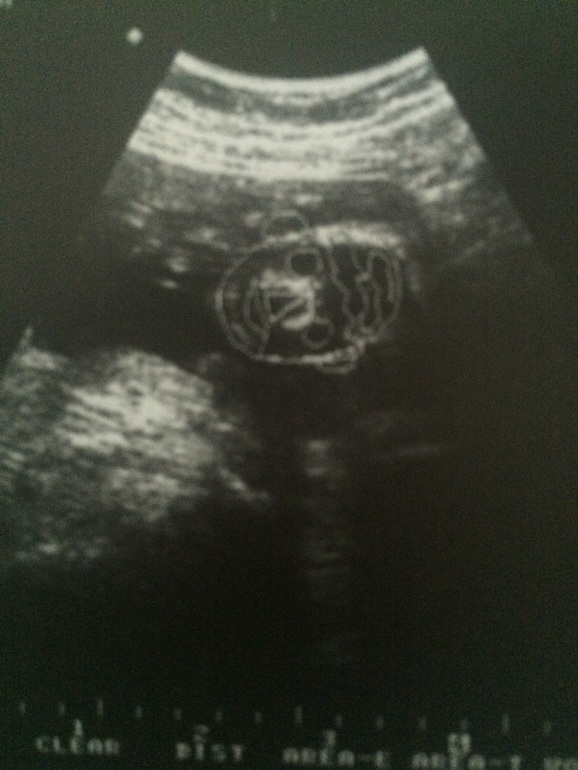

Второй скрининг ( узи)!

УЗИ, КТГ, доплерКак я этого ждала! Как и все будущие мамы переживала за детку, как ему там? Хорошо ли? Всего ли хватает ? Тем более недавняя простуда моя и прочие стрессы мамы. Доктор бесплатного узи ( приятно отметить) очень любит свою работу! Все показал и рассказал в подробных подробностях))) и даже записал на диск ( это конечно платно) , общий итог: у нас ВСЕ ОТЛИЧНО!!!! Боже, СПАСИБО!!!!

А ждем мы рыцаря, маминого помощника и будущего покорителя женских сердец - сыночка!